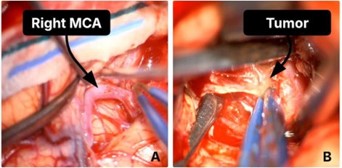

Given the lesion’s size and intraventricular extension, the patient underwent pterional craniotomy for debulking as the first step of tumor excision (Figure 2). shows the tumour debulking and the identification of the right Middle Cerebral Artery (MCA). As the MCA was promptly identified during the operation, local irrigation with papaverine solutions was applied. Postoperatively, the patient was transferred again to the ICU, and CT head showed the extent of debulking (Figure 3). Two days post-op, the patient developed anisocoria, and the repeated CT scan showed a right-sided MCA infarct with extensive midline shift (Figure 3). No matter the intra-operative papaverine irrigation, MCA vasospasm was quite evident. Therefore, we did not continue with further endoscopic transsphenoidal resection. The patient subsequently succumbed to complications.